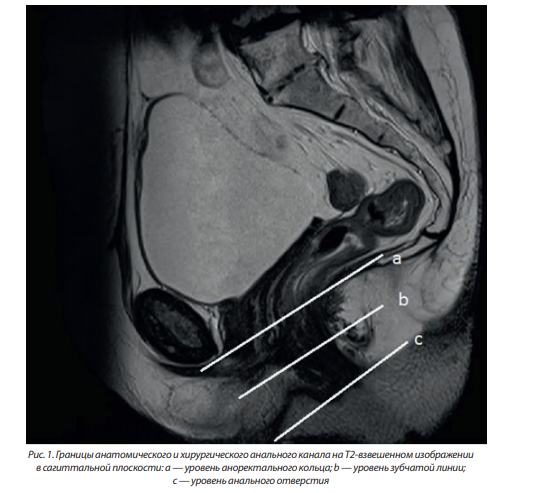

Особенности МР-анатомии аноректальной области

Аноректальная область является той зоной, где формируется основная проктологическая патология. В этой области выделяют анальный канал, идущий от кожи перианальной области до «зубчатой линии», выше которой начинается слизистая прямой кишки. Длина анального канала составляет от 1,5 до 3 см. Иногда выделяют «хирургический анальный канал», он несколько длиннее — до 5 см, идет выше зубчатой линии и достигает аноректального кольца, образованного пуборектальной мышцей, за счет чего кишка в этом месте меняет свое направление. Дистальной границей анального канала служит анальное отверстие, где граничат кожный покров перианальной области и эпителиальная выстилка анального канала, или анодерма, представленная многослойным плоским неороговевающим эпителием. На МРТ анальное отверстие отдельно не визуализируется, однако его уровень совпадает с дистальной границей мышечных волокон наружного сфинктера. Наиболее информативной для визуализации уровня анального отверстия является сагиттальная плоскость (рис. 1).

Границей между анальным каналом и собственно прямой кишкой является «зубчатая линия», ее можно увидеть во время ректоскопии, но нельзя определить при пальпации. Зубчатая линия образована на месте эмбриональной мембраны и имеет большое значение. Анатомически зубчатая линия представляет зону смыкания многослойного плоского эпителия анодермы и однослойного цилиндрического или кубовидного эпителия слизистой оболочки прямой кишки. Зубчатая линия не видна на МРТ, однако ее уровень можно определить по окончанию так называемых анальных столбов — вертикальных складок слизистой оболочки, в синусах между которыми располагаются устья анальных желез (крипты). Ниже зубчатой линии иннервация осуществляется соматической нервной системой (все манипуляции в этой области болезненные для пациента), а выше — вегетативной нервной системой (слизистая не чувствительна к манипуляциям). Выше зубчатой линии кровоснабжение осуществляется из системы верхних и средних геморроидальных сосудов, ниже — из системы нижних геморроидальных сосудов. Анальные столбы оптимально визуализируются на сагиттальных Т2-взвешенных изображениях (рис. 1).

Проксимальной границей хирургического анального канала служит аноректальное кольцо, располагающееся на уровне лобково-прямокишечной мышцы и дистального леватора ануса. На уровне аноректального кольца прямая кишка формирует изгиб кзади — аноректальный угол (рис. 1).